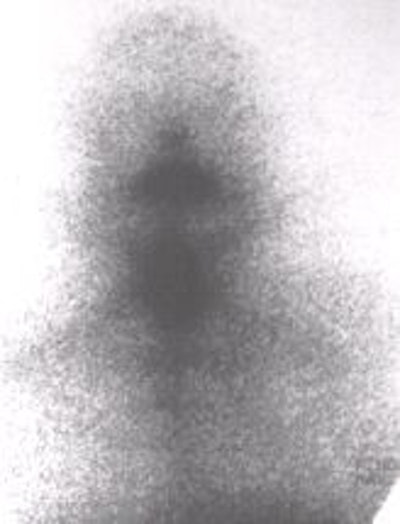

![]() ![]() ![]() |

| Diagnostic scans at 24 hours with 0.3 mCi 123I. No stunning effect is seen on these scans. Images courtesy of Dr. Hee Myung Park. |